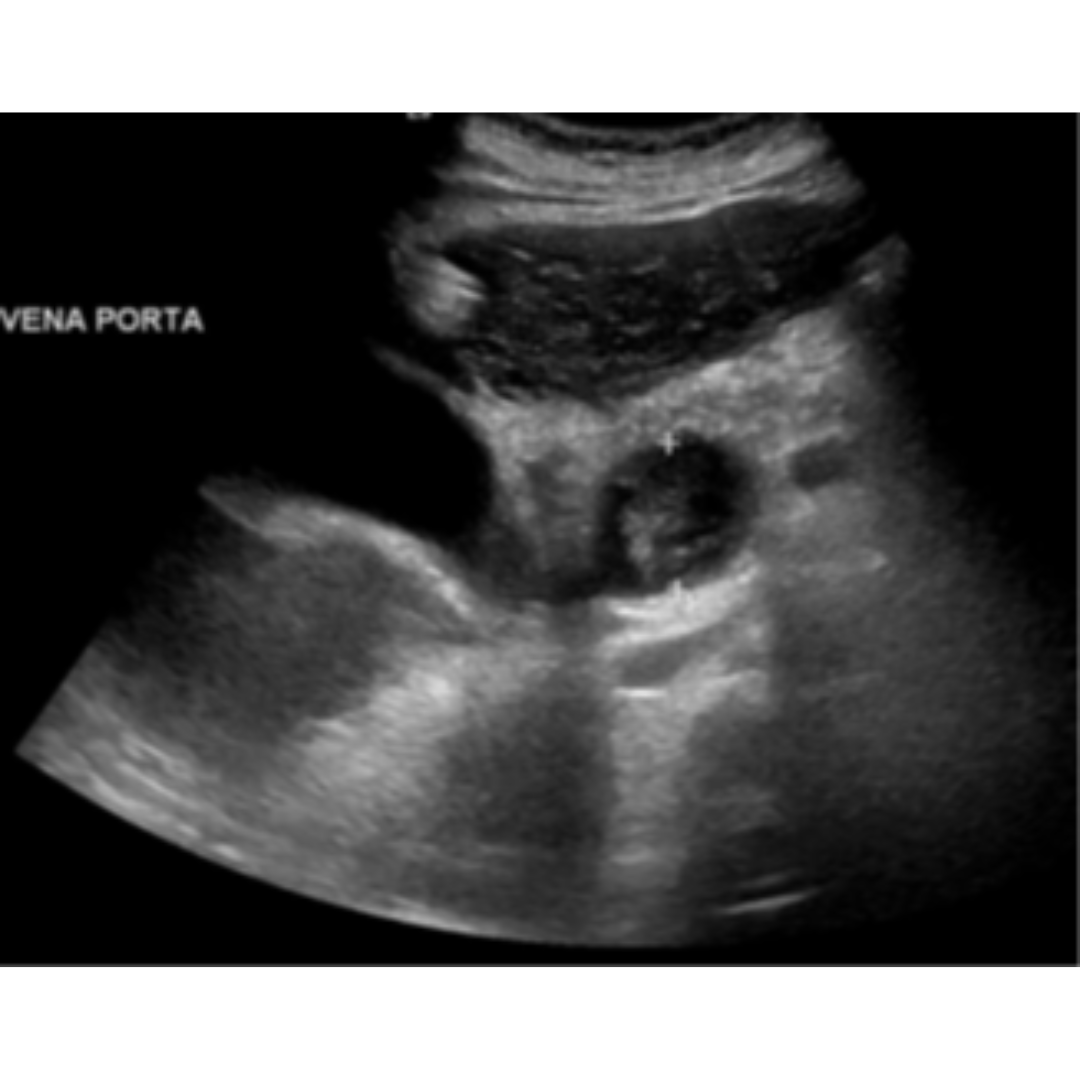

Diámetro de la Vena Porta

Se considera alterada partir de los 13 mm, la medición debe realizarse con el transductor en la región epigástrica o subxifoidea, con una leve inspiración para ver la vena porta posterior al lóbulo izquierdo. Si bien es un dato importante puede verse afectado por la posición del paciente, la respiración, el ayuno, otras causas como el flujo hepatofugo o la colateralidad portosistémica. Cuando esta se encuentre muy distendida es importante buscar posible trombosis asociada (figura 3 y 4).

Figura 3: Vena porta de tamaño aumento con diámetro de 18 mm.

Figura 4: Vena porta dilatada en su segmento extrahepático 2,5 cm con material hipoecogénico, compatible con trombosis que se prolonga craneal a la mesentérica superior